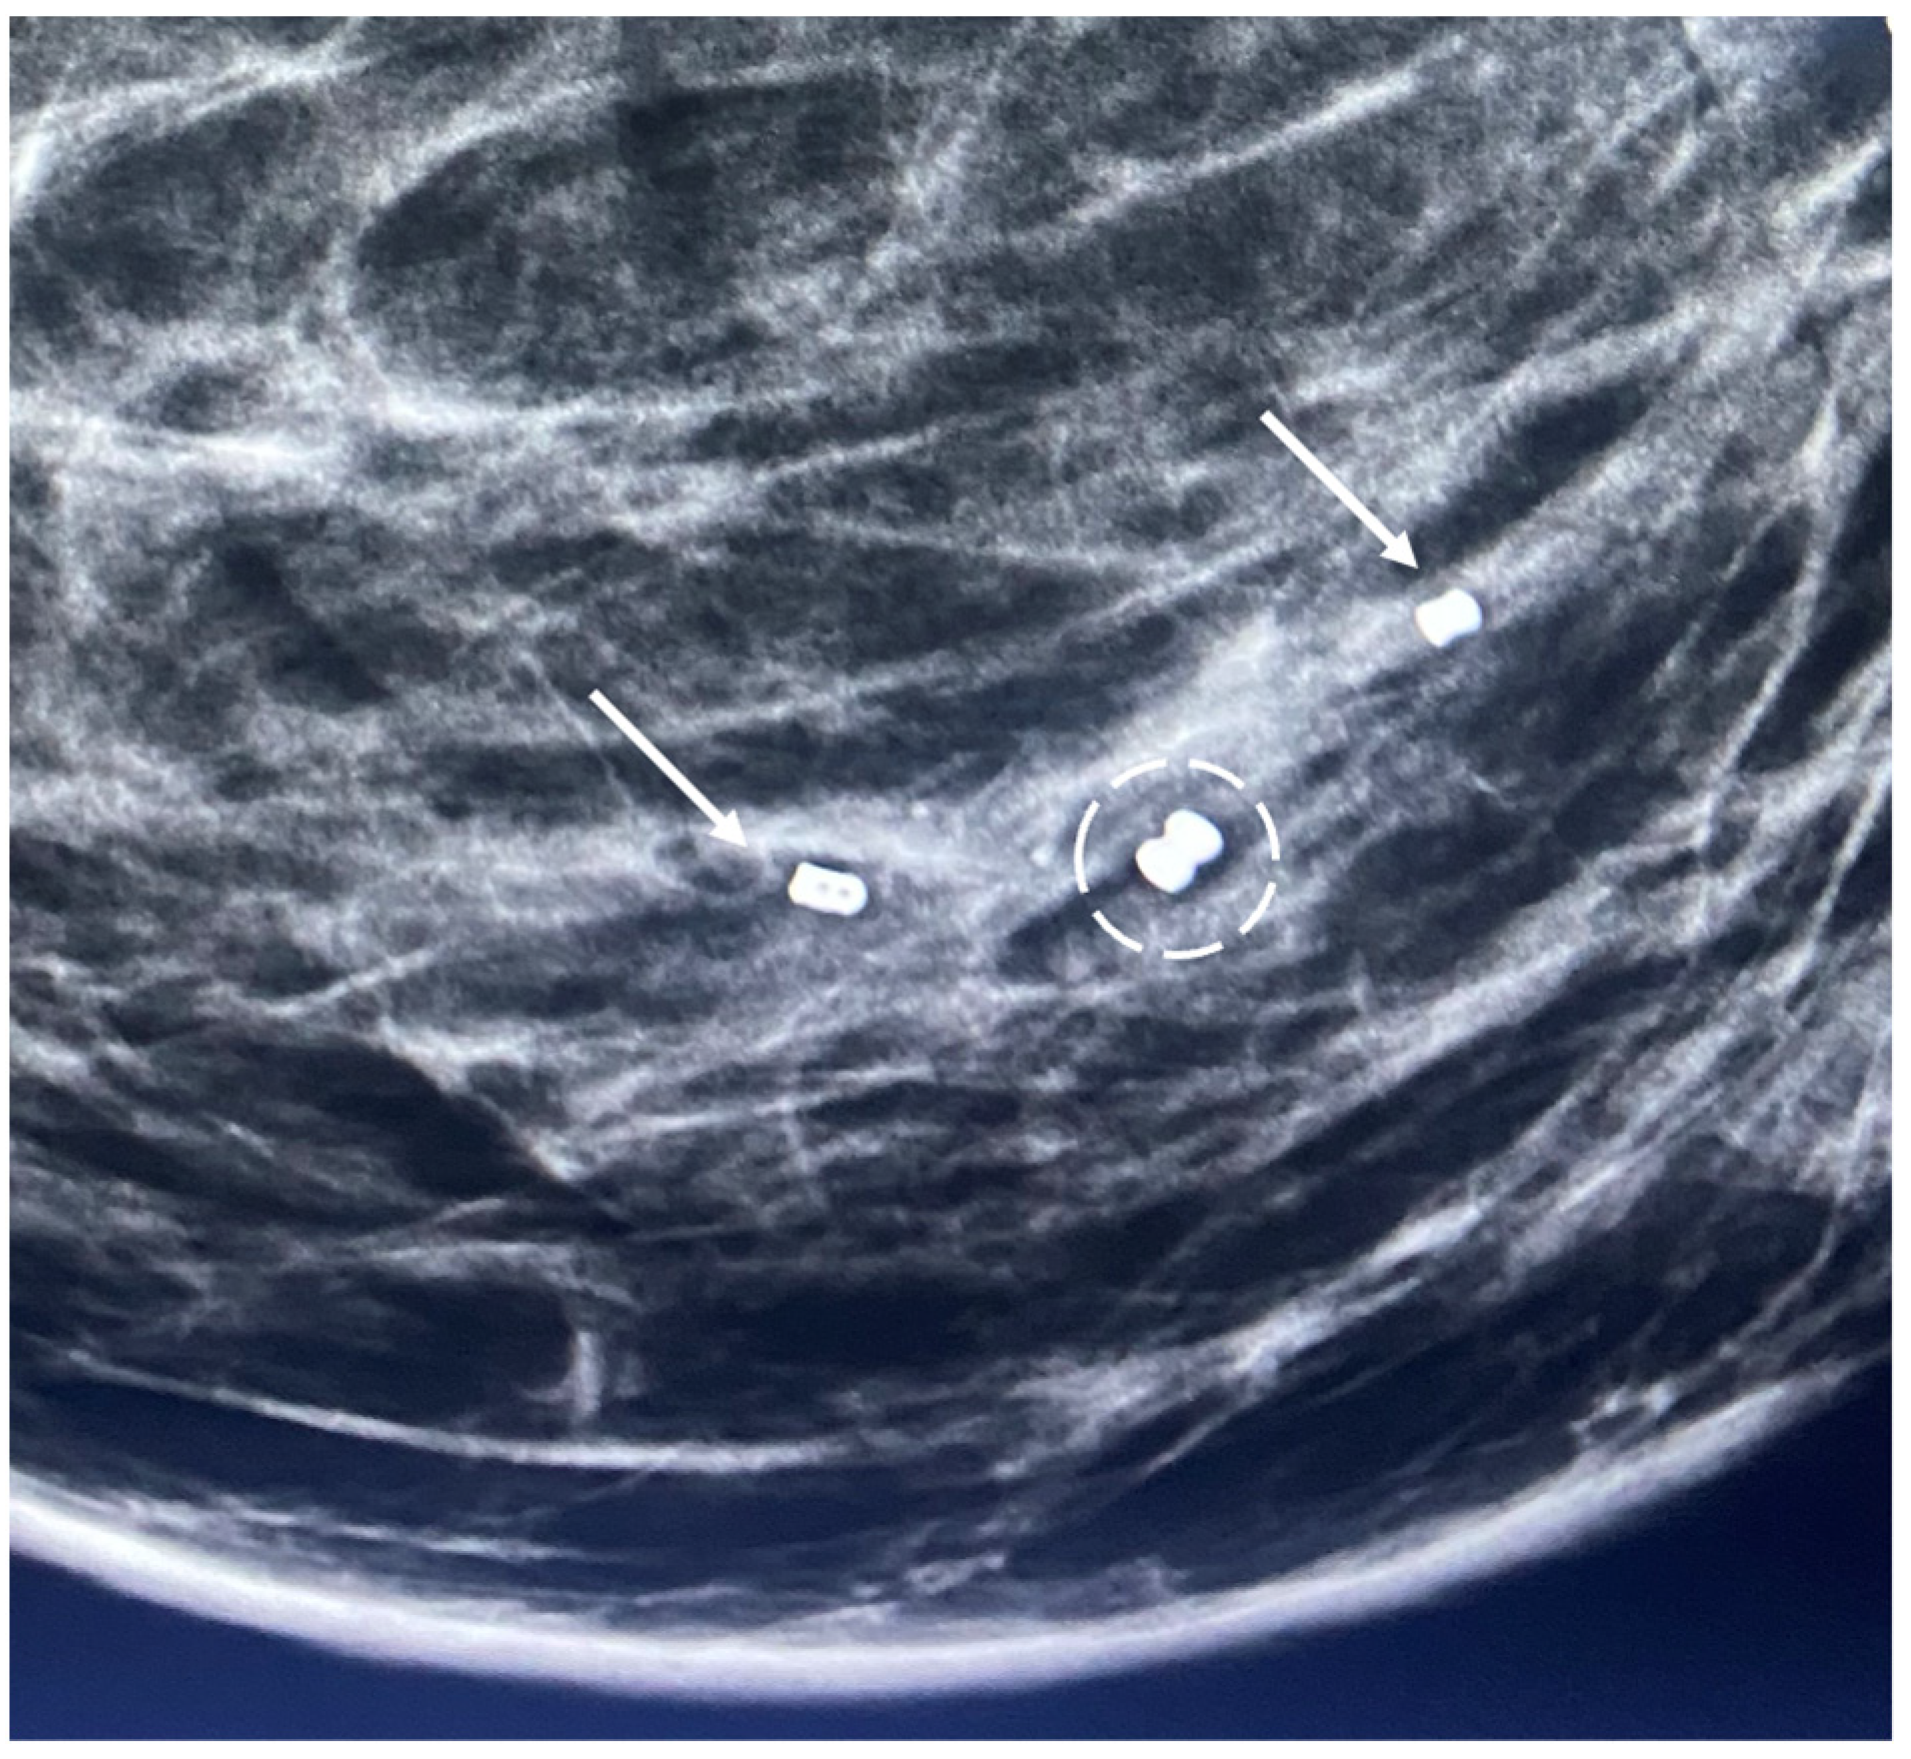

Generally, a single biopsy site marker is sufficient for marking the site of most breast cancers. However, patients with a wide span of disease may benefit from placement of two or more ultrasound-visible markers to outline or bracket the borders of the cancer to improve targeting of the cryoablation treatment (Figure 7).

Figure 7.

Mammogram showing the metal components (indicated arrows) of two ultrasound-visible biopsy site markers on opposite sides of the original metal biopsy site marker (encircled by hash marks) that was placed at the time of the diagnostic needle biopsy. The original biopsy site marker was not an ultrasound visible.